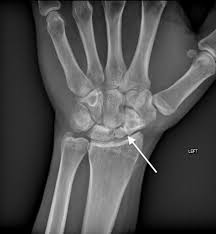

Fractura Del Hueso Escafoides De La Muneca Scaphoid Fracture Of The Wrist Orthoinfo Aaos